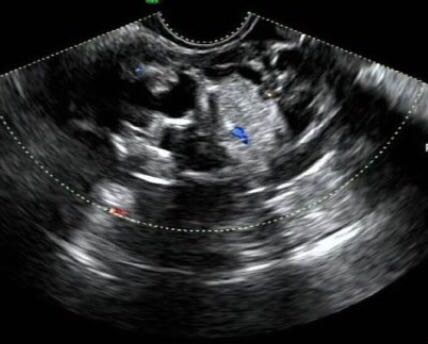

妇科查体: 外阴发育正常,宫颈常大光滑,子宫前倾位,常大,子宫左前方可触及一13cm左右囊性包块,活动度可,右附件区未触及明显异常. 辅助检查:盆腔超声:子宫前倾位,大小约6.8*4.1*3.8cm,子宫内膜厚约0.5cm。宫内见节育器反射,宫区未见明显占位性病变。子宫上方见13.1*10.8*7.4cm囊性肿物,形态略不规整,内呈液性伴分隔,部分分隔内伴细小点状回声,CDF部分分隔上可检出血流信号。双卵巢未显示。盆腔见2.1m游离液体。 盆腔CT:左卵巢囊实混合性肿瘤,囊腺瘤? 肿瘤标记物正常